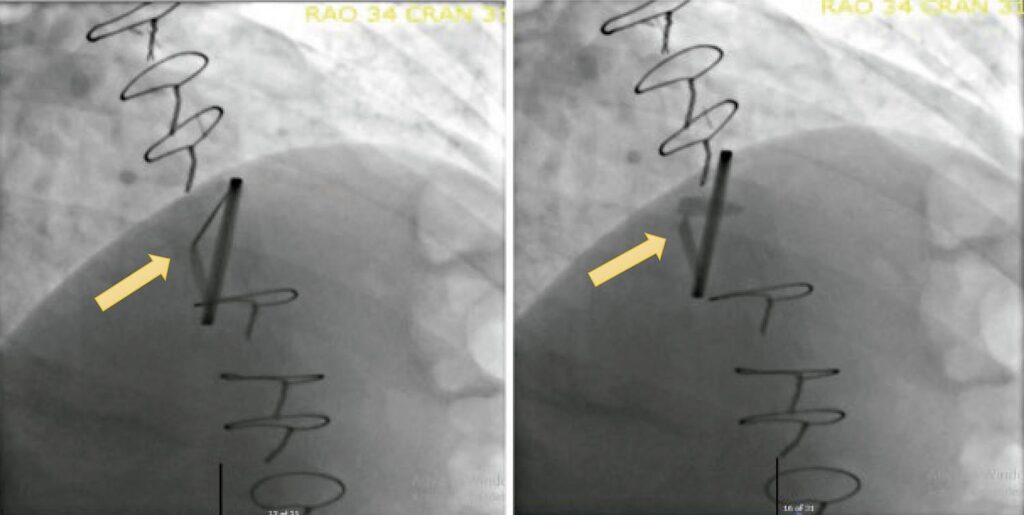

The authors present a case of mechanical mitral valve prosthesis dysfunction due to pannus. A Caucasian 43 years-old woman, with dyslipidaemia and hypertension with a history of infectious endocarditis of the mitral valve in 04/2022, presented with signs of infectious infiltration of both leaflets and severe mitral regurgitation. At this point, a cycle of antibiotic therapy was performed with ampicillin and flucloxacillin, with no agent being isolated (neither in blood cultures nor microbiological examination of the explanted valve). A double-disc mechanical valve prosthesis was implanted in the mitral position. The patients were hypocoagulated with a vitamin K antagonist (warfarin, with target INR levels of 2.5-3.5) and discharged from the hospital for outpatient follow-up.